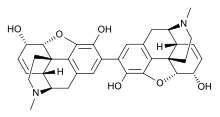

Morphides

- α-Chlorocodide (= chlorocodide)

- α-Chloromorphide (= chloromorphide)

- Bromocodide

- Bromomorphide

- Chlorodihydrocodide

- Chloromorphide

- Codide

Structures

| Morphides | ||||

α-chlorocodide α-chlorocodide |

β-chlorocodide β-chlorocodide |

Bromomorphide Bromomorphide | ||

Chlorodihydrocodide. Chlorodihydrocodide. |

Chloromorphide Chloromorphide |

Codide Codide | ||